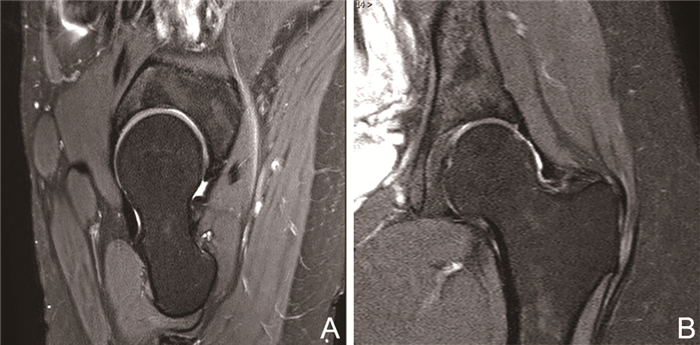

Value of proton density weighted image in evaluating acetabular labrum tears

ZHOU Rong-hua, ZHANG Hai-long, CHENG Xiao-guang, LIANG Wei, JIANG Wen

2023, 21(2): 283-287. doi: 10.16766/j.cnki.issn.1674-4152.002865

Abstract:

Objective  To explore the reliability of proton density weighted image (PD-WI) in evaluating acetabular labrum tears.  Methods  Forty trauma hip pain out-patients (20 males and 20 females, age range: 27-65 years, mean age: 40 years) without obvious or slight trauma in Beijing Jishuitan Hospital from March 2019 to January 2020 were recruited and underwent acetabular labral magnetic resonance imaging scan that included PD-WI sequence to exclude acetabular labrum tears and exclude fracture, tumour, infection and other diseases in hip. The presence of acetabular labrum tear was evaluated according to PD-WI image instead of surgical outcome. Classification consisting of basal and substantial tears from previous histological studies was also determined by PD-WI image. All patients underwent surgery in 3 months after scanning. According to surgical outcome, the sensitivity, specificity and accuracy of PD-WI to evaluate acetabular labrum tears and kappa consistency test to evaluate tears and classification were acquired.  Results  The sensitivity, specificity and accuracy of PD-WI to evaluate anterior and lateral-superior acetabular labrum tears were 96.88% and 90.00%, 62.50% and 93.33%, 90.00% and 92.50%, respectively. The PD-WI diagnosis of acetabular labial tears and tear classification was in good agreement with the surgical results (anterior labrum tears: Kappa=0.655, P < 0.001; lateral-superior labrum tears: Kappa=0.806, P < 0.001; all types of tear: Kappa>0.75, P < 0.0001).  Conclusion  PD-WI could be regarded as a reliable imaging method to evaluate acetabular labrum tears and could be helpful for diagnosis and treatment option.